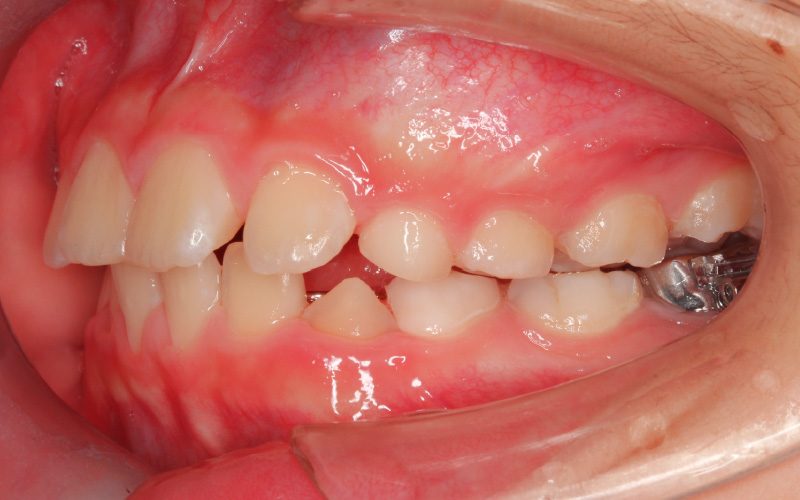

治療前

[11歳1か月]

顔立ちと咬み合せのために下顎の成長が必要と考え、まず顎関節の発育状態をチェックしました。その時重要な役割を果たすのがこの症例の場合MRIです。円板転位は初期で、2次軟骨も成長スパート直前の状態であるとわかりました。

まず歯の配列のみを考えている装置を外し、歯を並べる準備ができるまで、咬み合せを安定させるスタビライゼーションスプリントを1日12〜15時間程(主に夜間)装着してもらい、定期的にチェックして下顎の成長を観察しました。